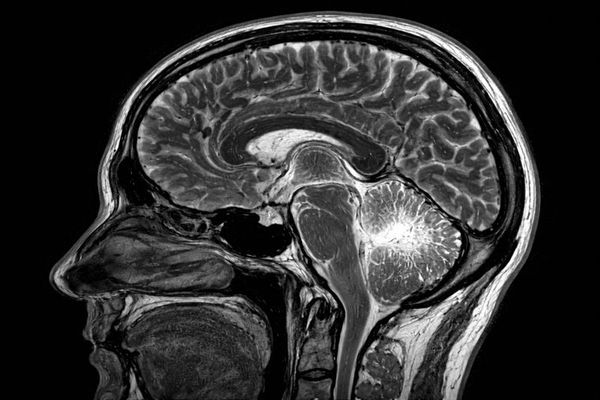

Точная диагностика эпилепсии играет ключевую роль в выборе эффективной тактики лечения и контроле заболевания. Современные методы нейровизуализации позволяют выявлять даже минимальные структурные изменения, которые могут быть причиной приступов. МРТ мозга при эпилепсии считается одним из наиболее информативных исследований, применяемых в неврологической практике.

МРТ мозга при эпилепсии — это высокоточный метод магнитно-резонансной томографии, направленный на детальное изучение структур головного мозга у пациентов с эпилептическими приступами. Исследование проводится без лучевой нагрузки и позволяет получить послойные изображения тканей. Такой подход особенно важен при сложных или атипичных формах заболевания.